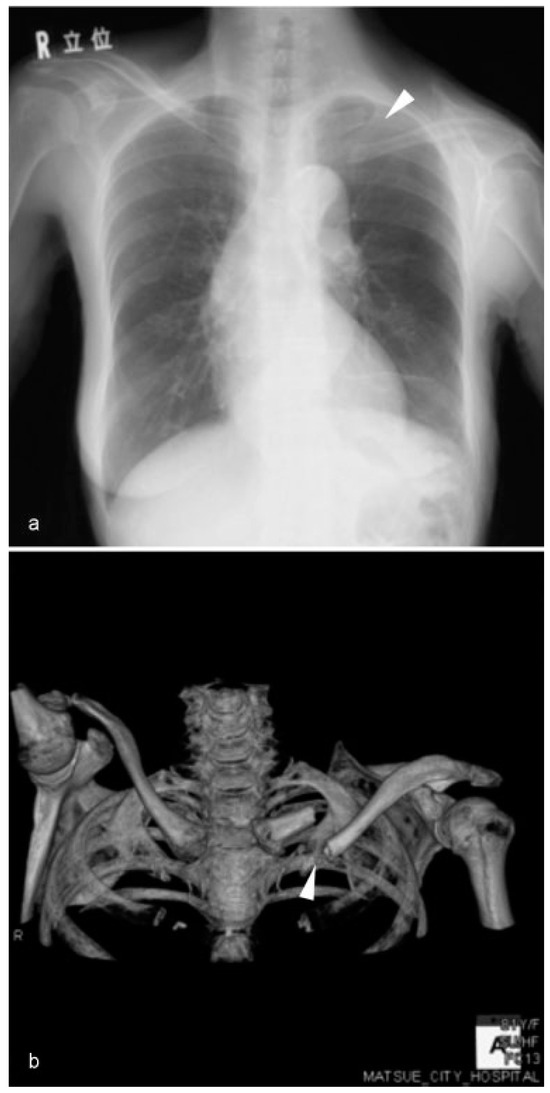

One month after postoperative radiotherapy, the left clavicle was fractured when she raised her left hand and took hold of the handrail of a flight of stairs. She complained of limitation in her left shoulder movement without any pain and was referred to the department of orthopedics. Physical examination showed anteromedial displacement of her left shoulder. X-ray and CT scan revealed a fracture at the inner two-thirds of the clavicle (Figure 4). The patient chose con-servative treatment.

Figure 4. Chest X-ray (a) and 3DCT (b) showed a fracture of the left clavicle (arrowhead).